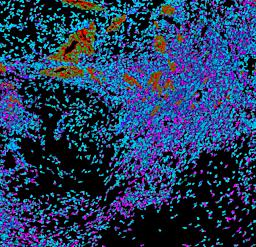

Pancreatic ductal adenocarcinoma is a lethal disease with limited treatment options and poor survival. We studied 83 spatial samples from 31 patients (11 treatment-naïve and 20 treated) using single-cell/nucleus RNA sequencing, bulk-proteogenomics, spatial transcriptomics and cellular imaging. Subpopulations of tumor cells exhibited signatures of proliferation, KRAS signaling, cell stress and epithelial-to-mesenchymal transition. Mapping mutations and copy number events distinguished tumor populations from normal and transitional cells, including acinar-to-ductal metaplasia and pancreatic intraepithelial neoplasia. Pathology-assisted deconvolution of spatial transcriptomic data identified tumor and transitional subpopulations with distinct histological features. We showed coordinated expression of TIGIT in exhausted and regulatory T cells and Nectin in tumor cells. Chemo-resistant samples contain a threefold enrichment of inflammatory cancer-associated fibroblasts that upregulate metallothioneins. Our study reveals a deeper understanding of the intricate substructure of pancreatic ductal adenocarcinoma tumors that could help improve therapy for patients with this disease.